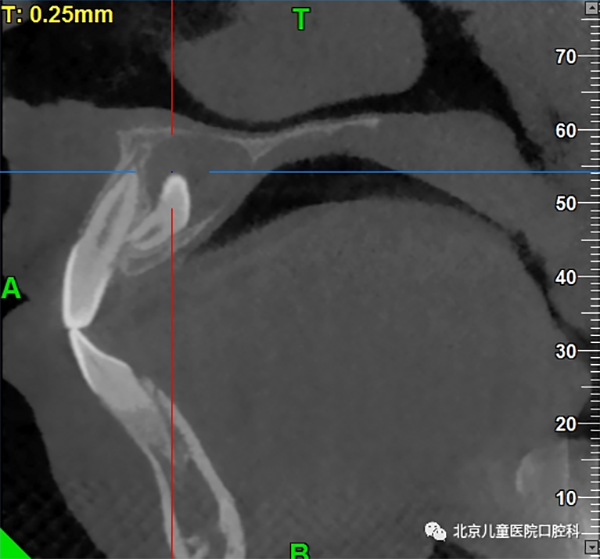

多生牙可发生在牙弓任何位置,多见于上颌前牙区,通常会占用正常牙齿在牙列中的位置,破坏正常的牙弓形态,同时,由于不具备正常牙齿的外形而缺少与正常牙齿的邻接,容易造成食物嵌塞和滞留,导致牙龈组织发炎甚至引起龋齿的发生。更有甚者,占用了正常恒牙萌出的空间,挡了正常恒牙的“路”,使得正常恒牙无法顺利萌出。

颌骨内多生牙可造成囊性变形成含牙囊肿

少数长期埋伏在骨内的多生牙,由于牙冠周围的软组织病变,会形成颌骨内的囊肿。